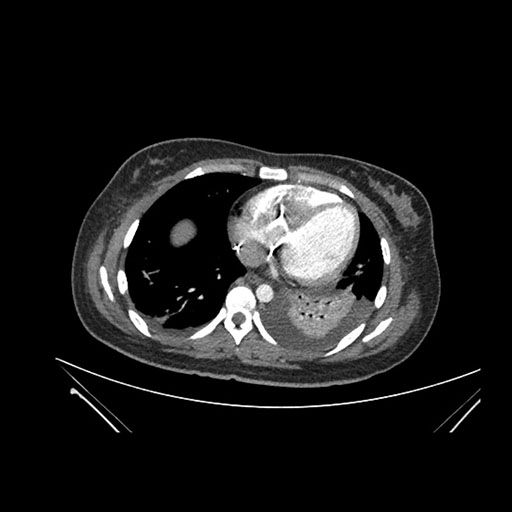

Axial Arterial